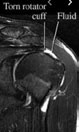

The rotator cuff is a group of four small muscles that originate from the shoulder blade and merge to form a common tendon that wraps around your humerus. Tears to the rotator cuff are quite a common injury to the shoulder. They have a very important role to aid in motion and stability of the shoulder.

Diagnosis of a rotator cuff tear requires the combination of a thorough physical examination, detailed history and review of any imaging that you’ve had. Other conditions can masquerade as a rotator cuff tear and a diagnosis cannot be made without these three aspects of your presentation. The shoulder requires a thorough physical examination by an experienced therapist, once the diagnosis is complete, a treatment plan is prepared to get you back to the things you love.

Rotator cuff tears are amongst the most common shoulder injuries that we treat at Action Rehab. They are more common later in life, and by the age of 60 up to 25% of the population can have a rotator cuff tear on MRI or ultrasound. Although rotator cuff tears are common, they are not always painful or symptomatic.